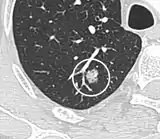

- A lung nodule abutting a pulmonary cyst is a rare finding, yet indicating cancer.[9]

- Bubble-like lucencies in the nodule indicate cancer:[9]

- Vascular convergence is where vessels converge to a nodule without adjoining or contacting the edge of the nodule, and is mainly seen in peripheral subsolid lung cancers.[9] It reflects angiogenesis.[9]